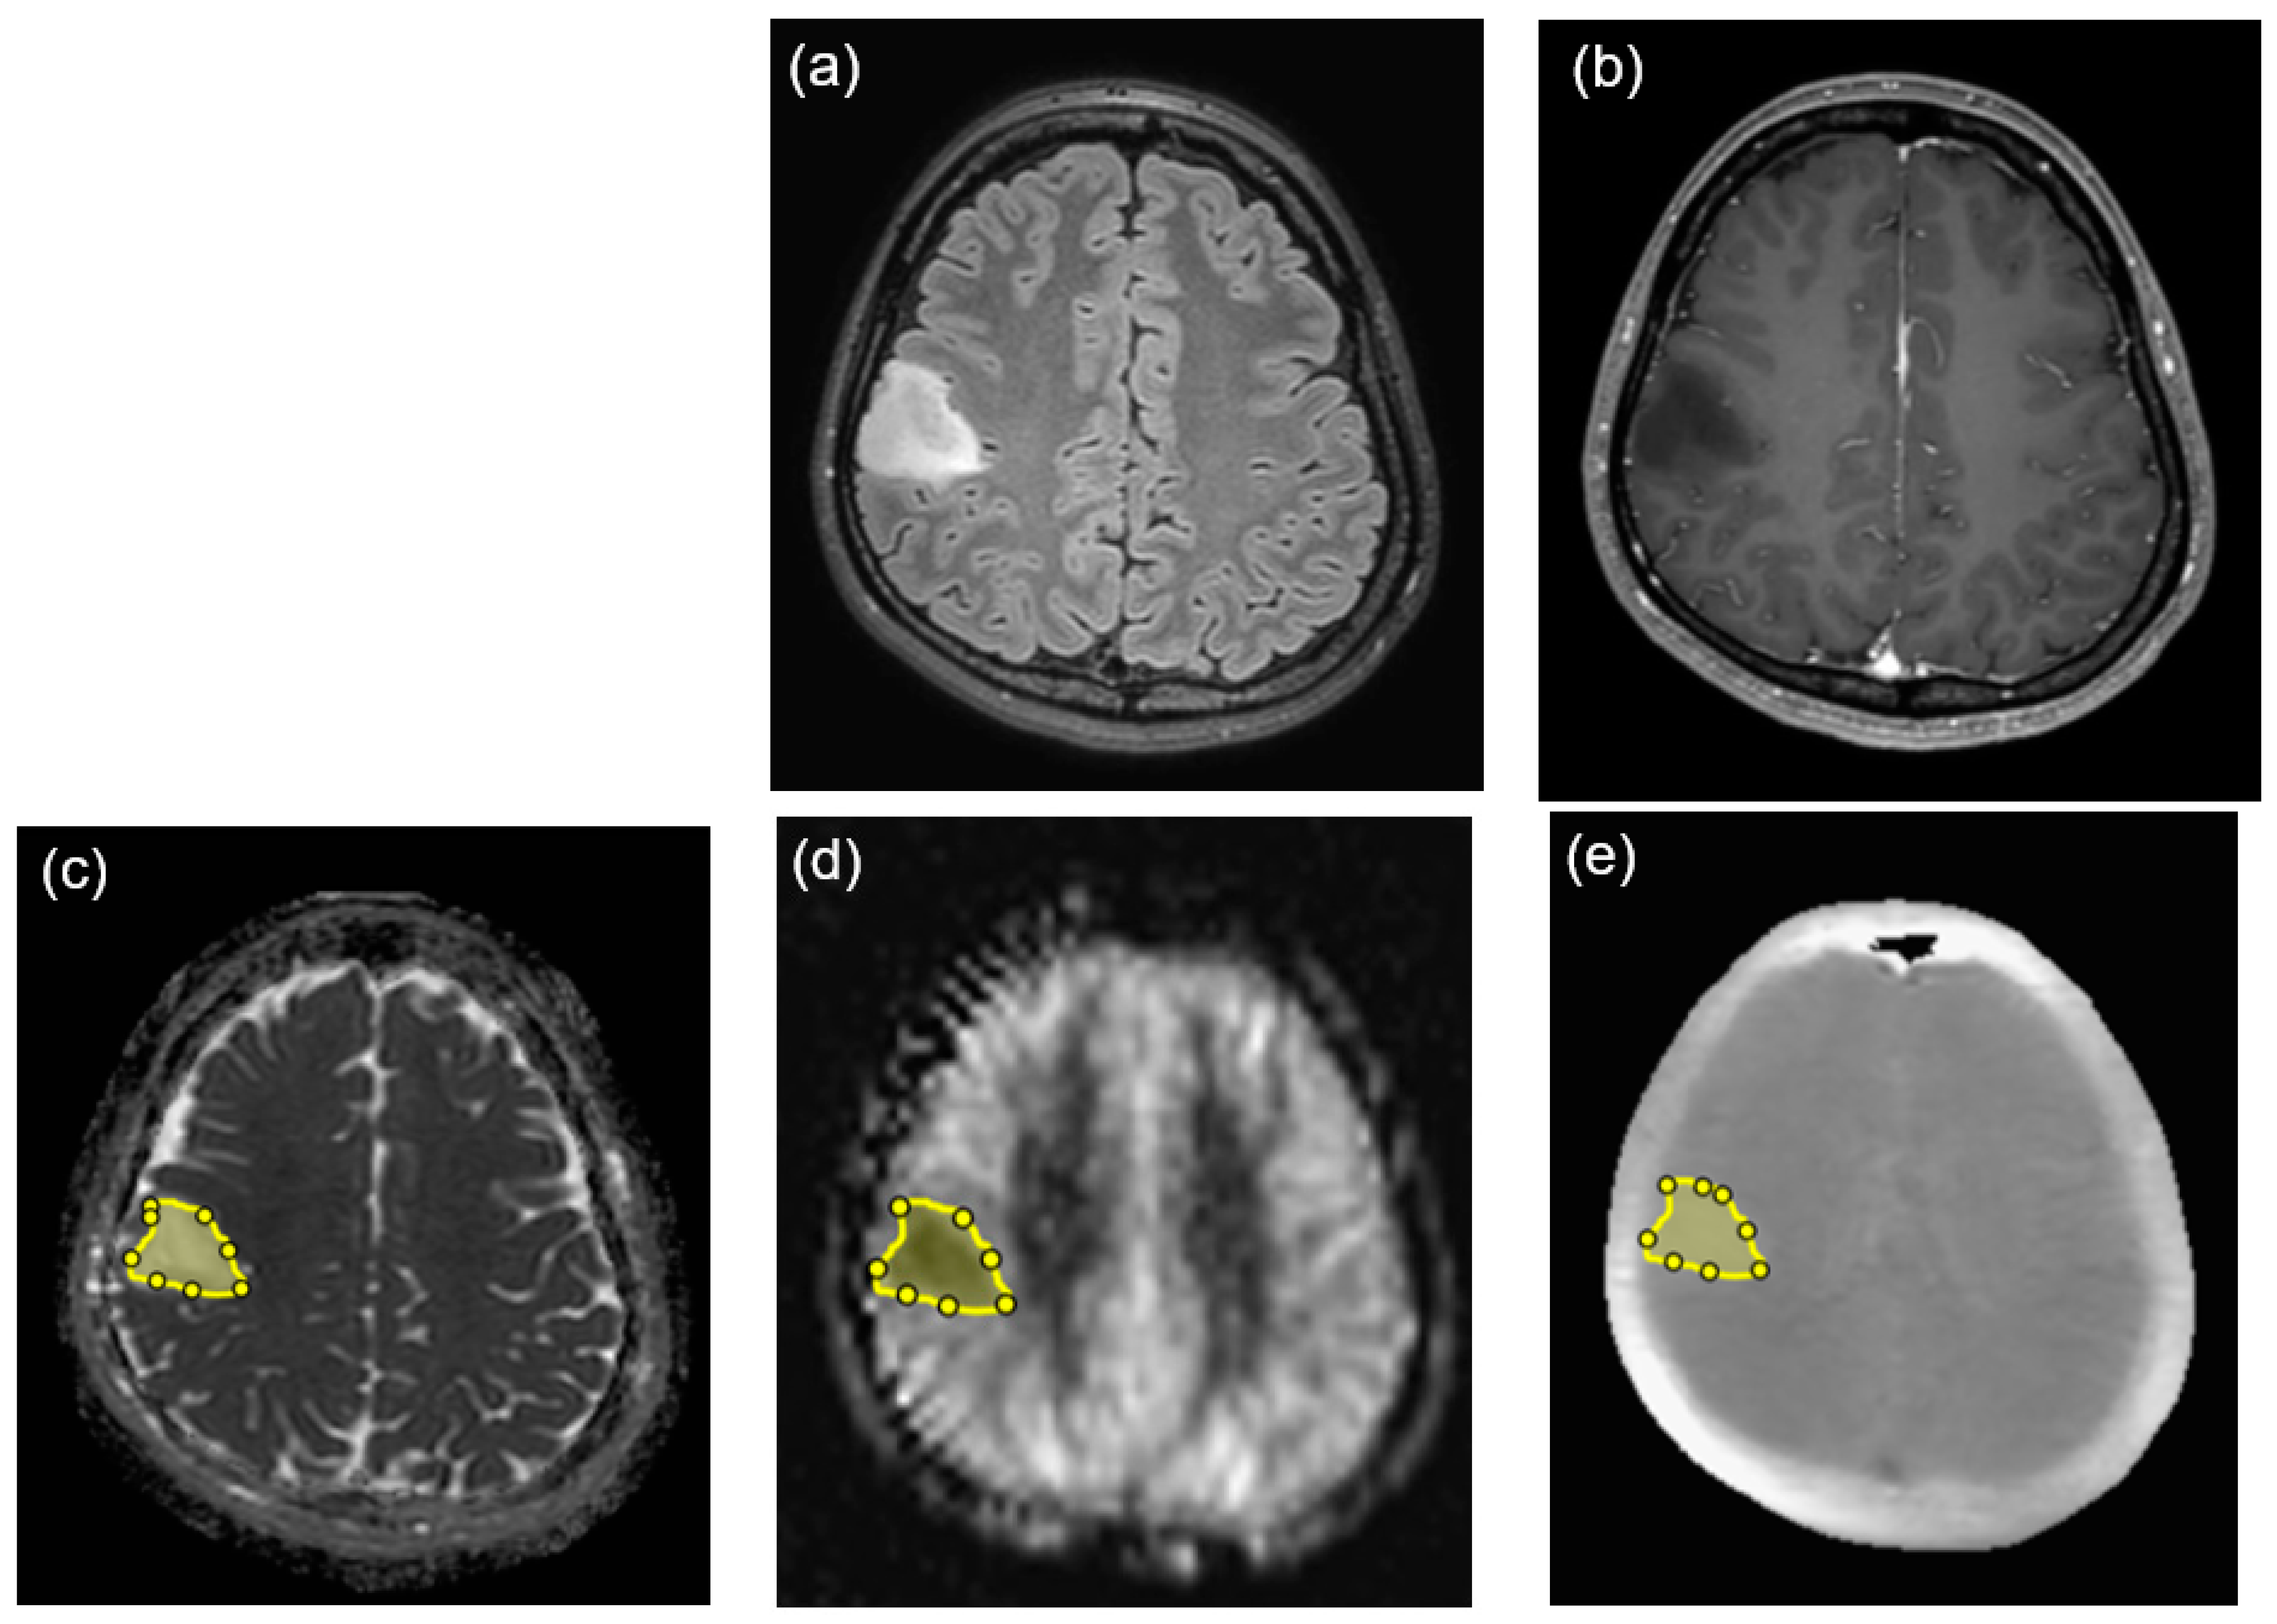

| M | 6 | 12 | F | Rt. frontal lobe | 50 | 100% resection | Paediatric-type diffuse high-grade glioma, H3-wildtype and IDH-wildtype, grade4 | Glioblastoma |

| M | 7 | 17 | M | Fourth ventricle | 44 | 70% resection | Medulloblastoma, non-WNT/non-SHH, grade 4 | Medulloblastoma |

| M | 8 | 5 | M | Fourth ventricle | 49 | 100% resection | Medulloblastoma, NOS, grade 4 | Medulloblastoma |

| M | 9 | 3 | F | Rt. lateral ventricle | 58 | 100% resection | Atypical teratoid/rhabdoid tumor, grade 4 | Atypical teratoid/rhabdoid tumor |

| M | 10 | 11 | F | Lt. basal ganglia | 50 | 80% resection | Germinoma, ICD/3 | Germinoma |

| M | 11 | 22 | M | Pineal region | 28 | 100% resection | Germinoma, ICD/3 | Germinoma |

| M | 12 | 27 | M | Pineal region | 33 | Biopsy | Germinoma, ICD/3 | Germinoma |

| M | 13 | 0 (1 month) | M | Fourth ventricle | 45 | 90% resection | Immature teratoma, ICD/3 | Immature teratoma, |

| M | 14 | 6 | M | Pineal region | 39 | Biopsy | Immature teratoma, ICD/3 | Immature teratoma |

| M | 15 | 12 | M | Suprasellar region | 40 | Biopsy | Mixed germ cell tumor, ICD/3 | germinoma and immature teratoma |

| B | 16 | 30 | F | Rt. parietal lobe | 36 | Biopsy | Astrocytoma, IDH-mutant, grade 2 | Diffuse astrocytoma without microvascular proliferation, or necrosis Homozygous deletion of CDKN2A/B was not detected. |

| B | 17 | 22 | M | Lt. thalamus~midbrain | 19 | 60% resection | Diffuse low-grade astrocytoma, NOS | Diffuse astrocytoma, IDH-wildtype without microvascular proliferation, or necrosis No TERT promoter mutation, EGFR gene amplification, or +7/−10 chromosome copy-number alterations were detected. |

| B | 18 | 30 | F | Lt. thalamus~hypothalamus | 15 | Biopsy | Diffuse low-grade astrocytoma, NOS | Diffuse astrocytoma, IDH-wildtype without microvascular proliferation, or necrosis No TERT promoter mutation, EGFR gene amplification, or +7/−10 chromosome copy-number alterations were detected. |

| B | 19 | 3 | M | Lt. temporal lobe | 23 | 100% resection | Diffuse low-grade astrocytoma, NOS | Diffuse astrocytoma IDH wildtype without microvascular proliferation, or necrosis BRAF p.V600E mutation was detected. |

| B | 20 | 6 | F | Lt. thalamus~midbrain | 27 | Biopsy | Diffuse low-grade astrocytoma, NOS | Diffuse astrocytoma without microvascular proliferation, or necrosis Histone H3 K27M mutation was not detected. |

| B | 21 | 6 | F | Lt. frontal lobe | 52 | 80% resection | Angiocentric glioma, grade 1 | Angiocentric glioma |

| B | 22 | 26 | M | Rt. thalamus~midbrain | 18 | Biopsy | Pilocytic astrocytoma, grade 1 | Pilocytic astrocytoma |

| B | 23 | 1 | M | Fourth ventricle | 51 | 70% resection | Posterior fossa ependymoma, group A, grade 2 | Ependymoma |

| B | 24 | 9 | M | Lt. lateral ventricle | 87 | 70% resection | Supratentorial ependymoma, NOS, grade 2 | Ependymoma |

| B | 25 | 10 | F | Cerebellar vermis | 26 | Biopsy | Pilocytic astrocytoma, grade 1 | Pilocytic astrocytoma |